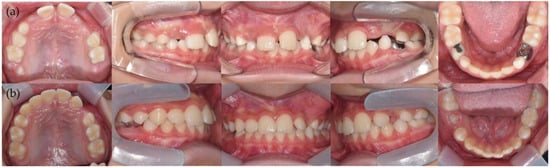

2. Case Report